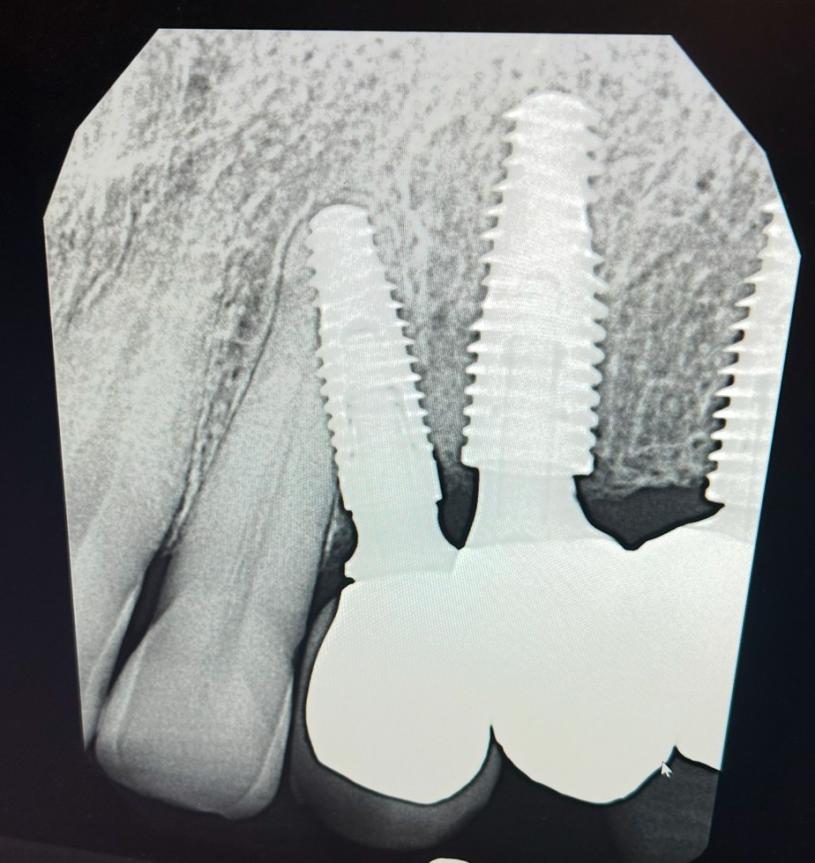

植牙由兩個部份組合而成:放進顎骨代替牙根的金屬圓筒,及鑽入金屬圓筒的基台螺絲。牙醫會在螺絲上安裝牙冠,令植牙呈牙齒形狀。根據美國口腔及頜面外科醫生協會(AAOMS),當顎骨太薄或太軟、無法承受植牙時,外科醫生可能會建議您進行植骨。因為如果骨骼無法支撐新植牙齒,這會導致植牙手術失敗。

您需要足夠健康的骨骼結構來適當地支撐新植入的牙齒。因此有些患者需要在植牙之前進行植骨。種植牙手術前的植骨可以強化牙齦組織下的骨骼,從而成功植入種植牙。

在植骨過程中,醫生可以從您身體的其他部份取出骨骼,或使用特製的植骨物料,移植到顎骨中。使用植骨物料是現今較常見的做法。在植骨後您需要等待數月,讓骨移植物料創造出新的、強壯的骨骼,確保植牙部位穩固。您或許只需接受小範圍的植骨,甚至可同時接受植牙手術,但所有情況均取決於牙醫的最後決定。「植骨」直接有關於植牙成功和失敗的關鍵,植牙患者千萬要特別小心注意,比價格之餘更要比較植入材料質素,切勿因小失大,一次成功的植骨足以令顎骨變得強壯,以後才能支撐起新植的牙齒,一勞永逸!